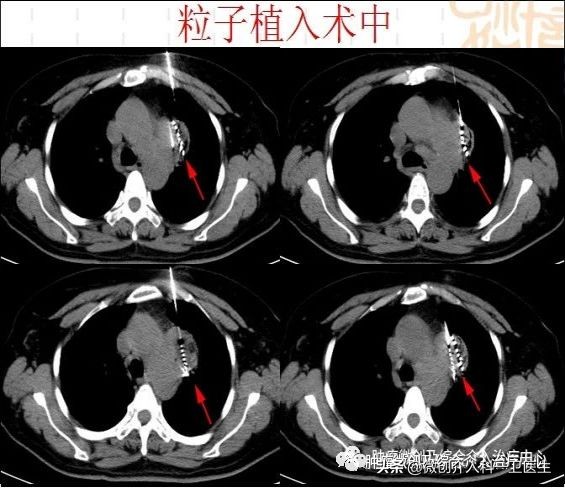

图3、4、5. 引导下精准穿刺进入肿瘤内部,将碘125粒子放入肿瘤内部达到治疗目的